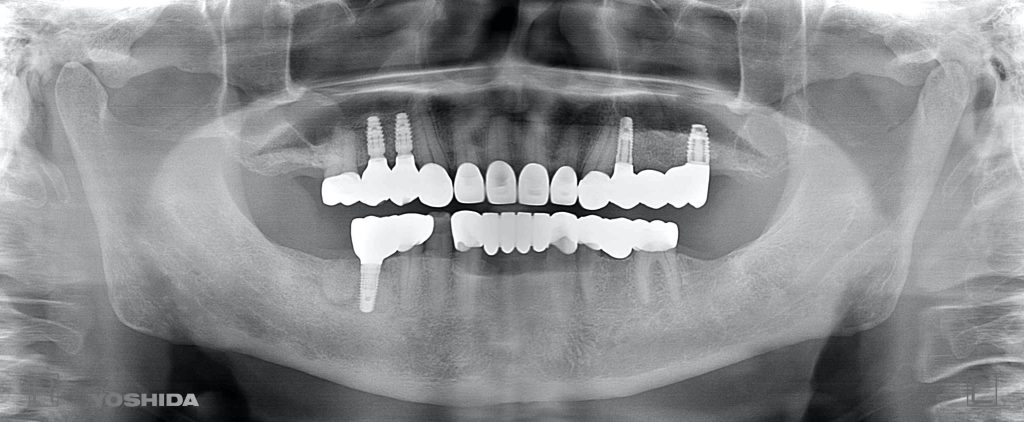

下記の症例は術前に綿密な治療計画を立案し、約10ヶ月ほどで咬合再構成を達成しました。

咬合再構成治療にかかる費用  約700万円(税抜)